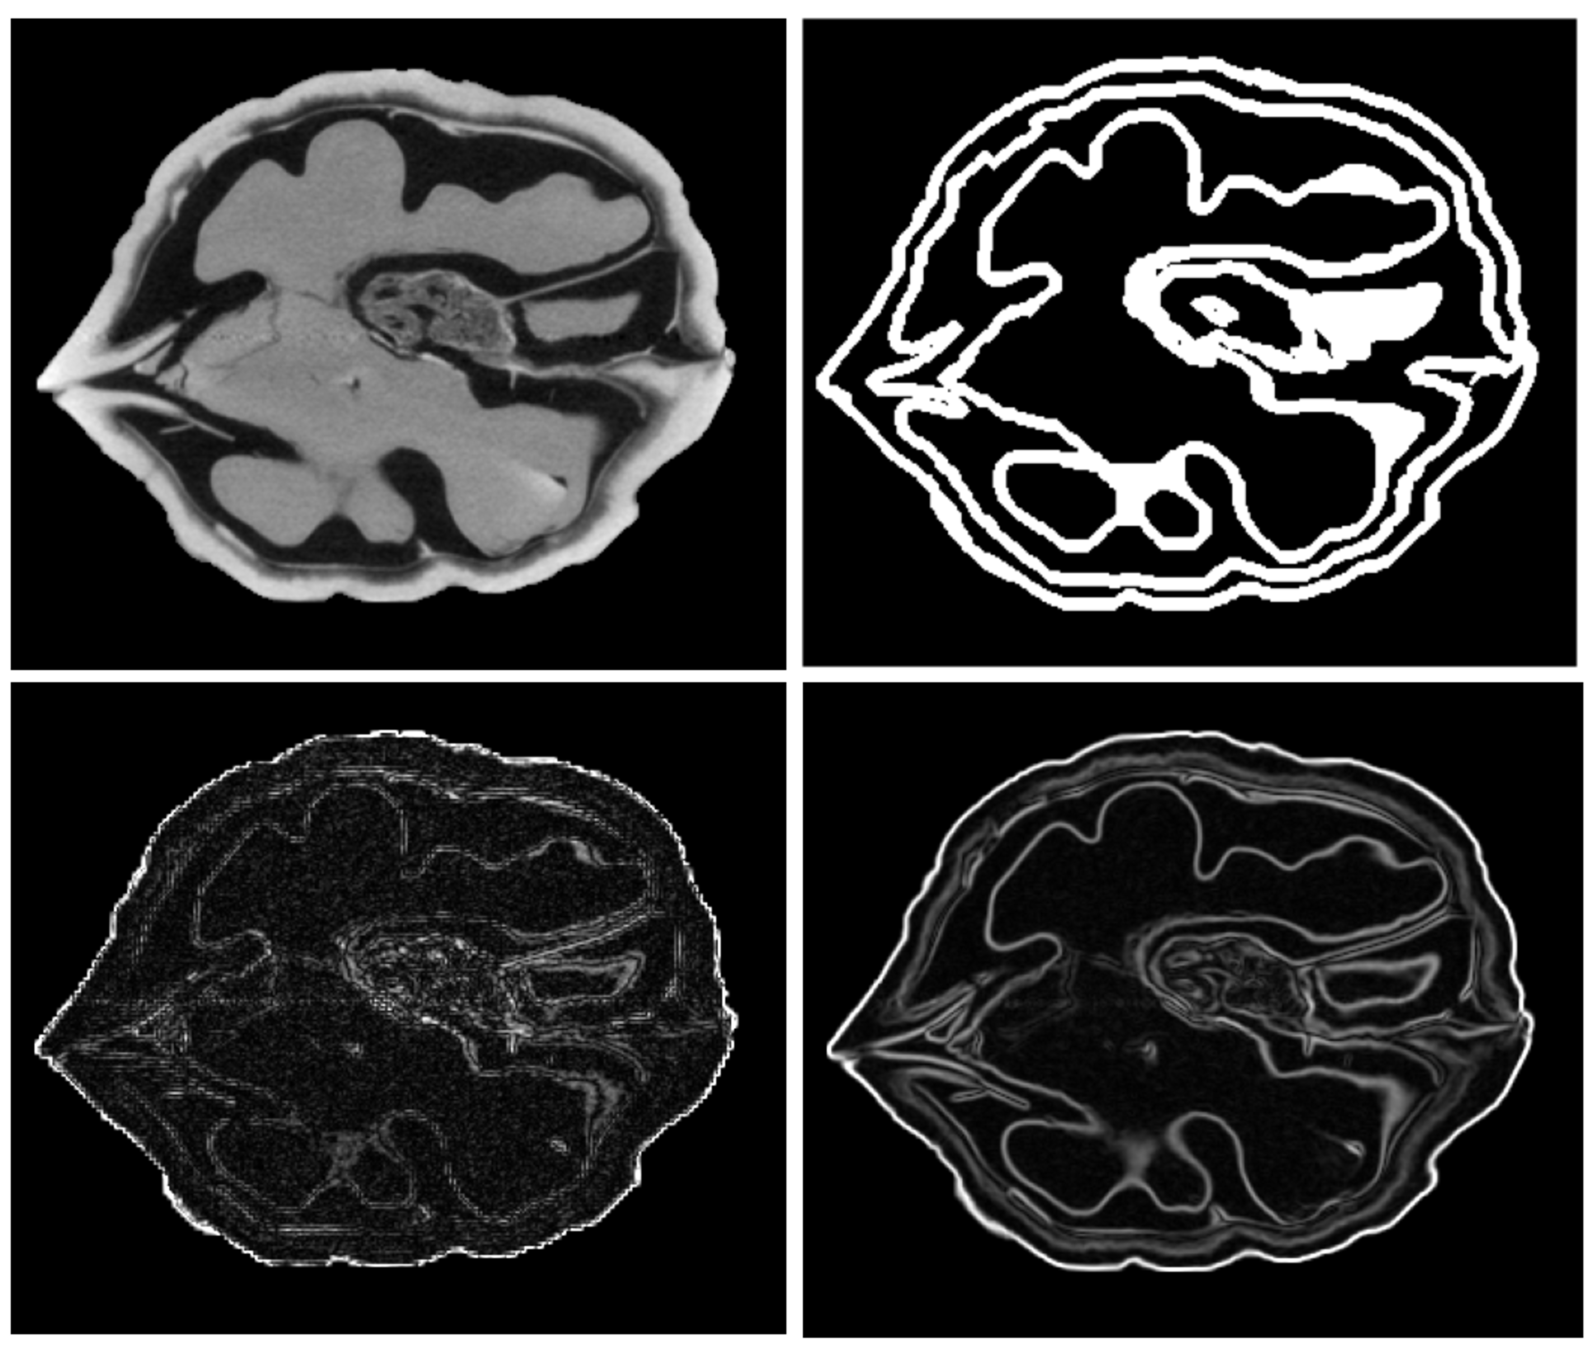

Consequences in 3D multimodal image resampling are currently under examination.

from the Preprint

- D. Poggiali, D. Cecchin, C. Campi, S. De Marchi, Oversampling errors in multimodal medical imaging are due to the Gibbs effect, doi:10.13140/RG.2.2.30924.13446/1